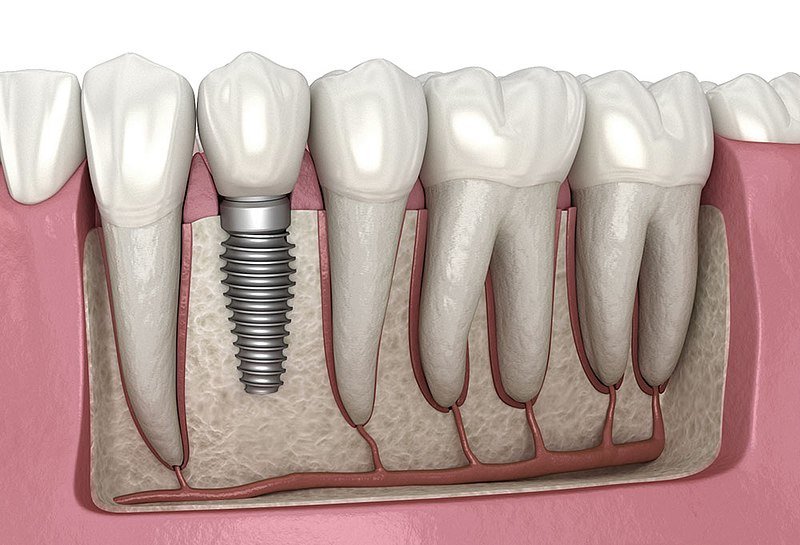

About Perfect Teeth Dental Clinic & Facial Aesthetic Centre "Healthy smile for whole family" Welcome to Perfect Teeth Dental Clinic, where we offer comprehensive dental care and facial aesthetic treatments. Our team of highly skilled professionals is dedicated to providing the best oral health solutions and enhancing your natural beauty. With a focus on services like root canal treatments, dental implants, invisalign, and complete faci... (Show more)